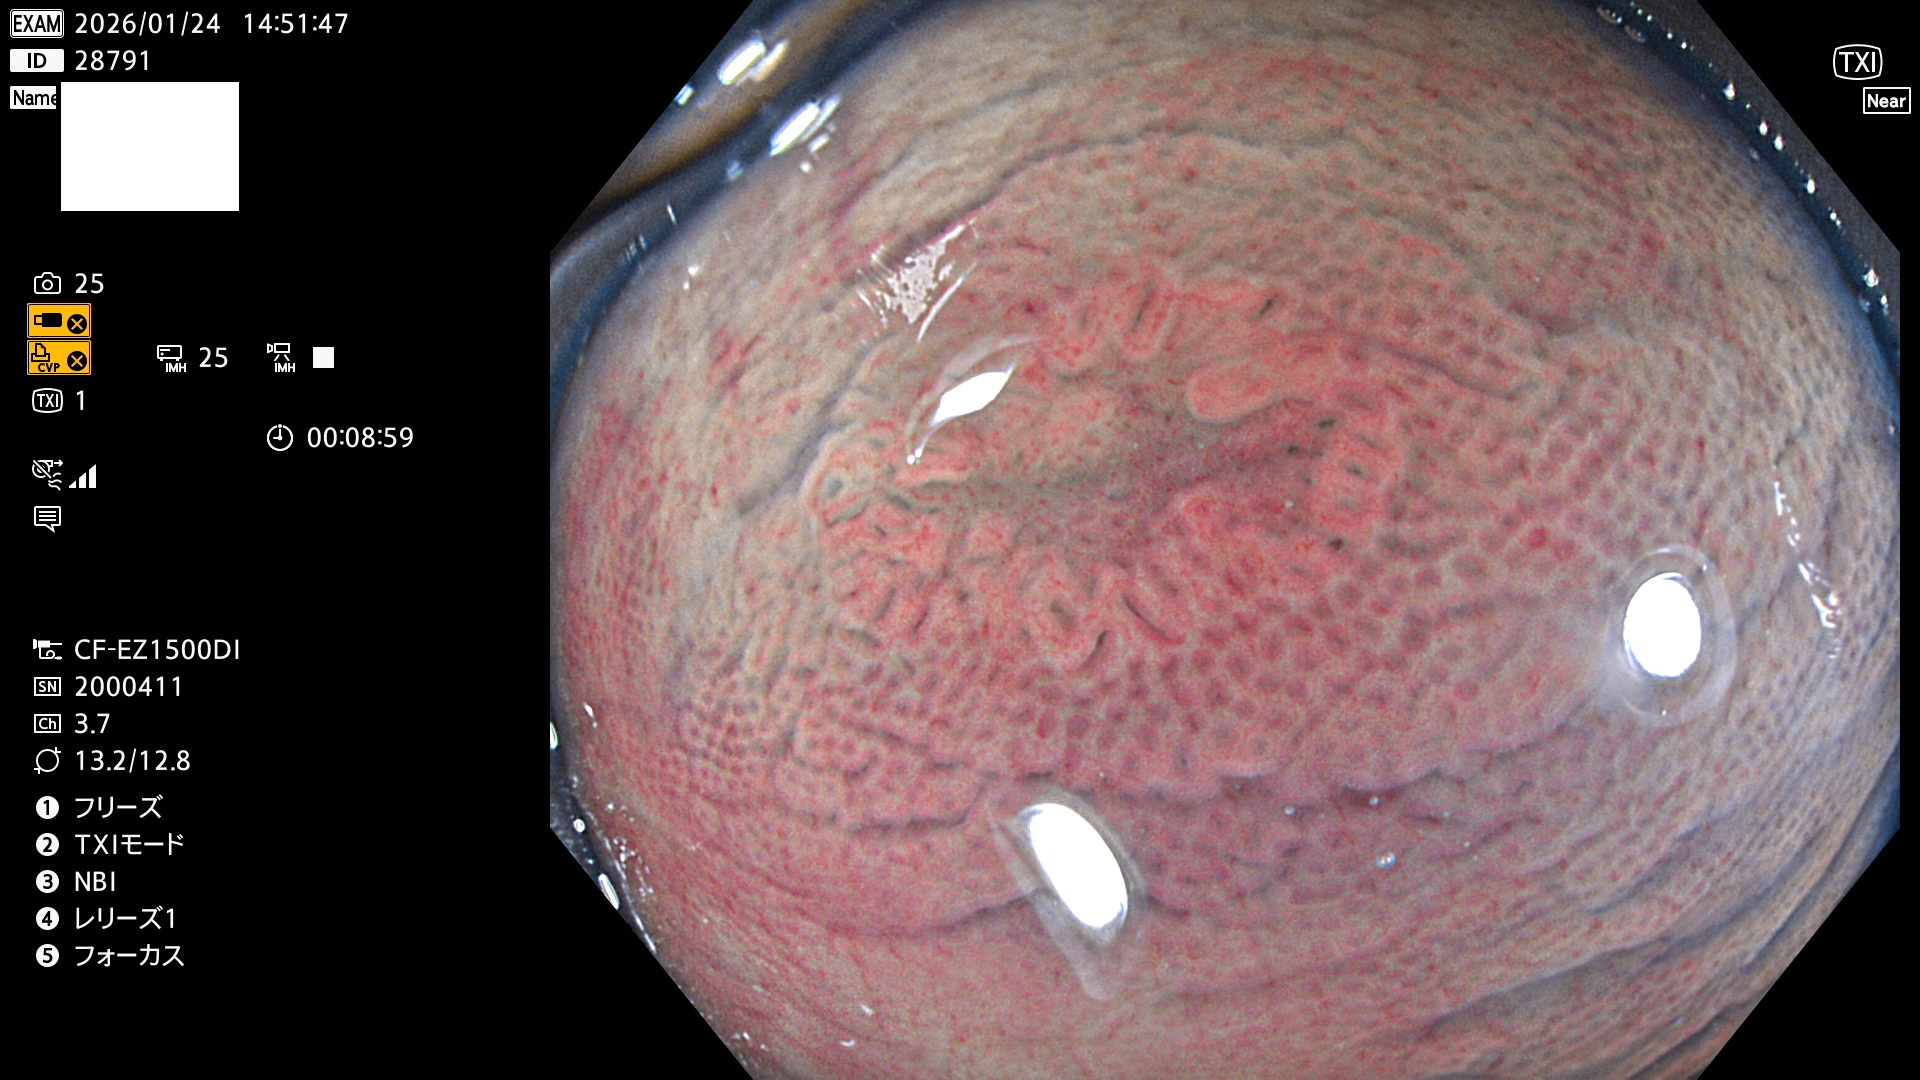

完全に平坦な物をUb、陥凹している物をUcと呼びます。Ubは認識が困難で、Ucはびらん(炎症)と紛らわしいために見落とされやすく、「内視鏡後・大腸癌」の原因になります。

専門的)Uc=De Novo癌? 内視鏡の解像度が低かった時代、このような説もありました。しかし今日の高精度内視鏡では良性の微小なUc型腺腫(APC遺伝子異常の腺腫)が日常的に見つかります。Ucこそが多段階発癌(Adenoma-Carcinoma Sequence)のMain Routeです。

毎週の検査(木・金・土・日)に発見されたUbとUc型・腺腫を、その週の日曜の夜にUPし1週間、提示します。

2026年1月22日〜1月25日の4日間(35件)4個 (Uc_ADR=4個/32人=13%)